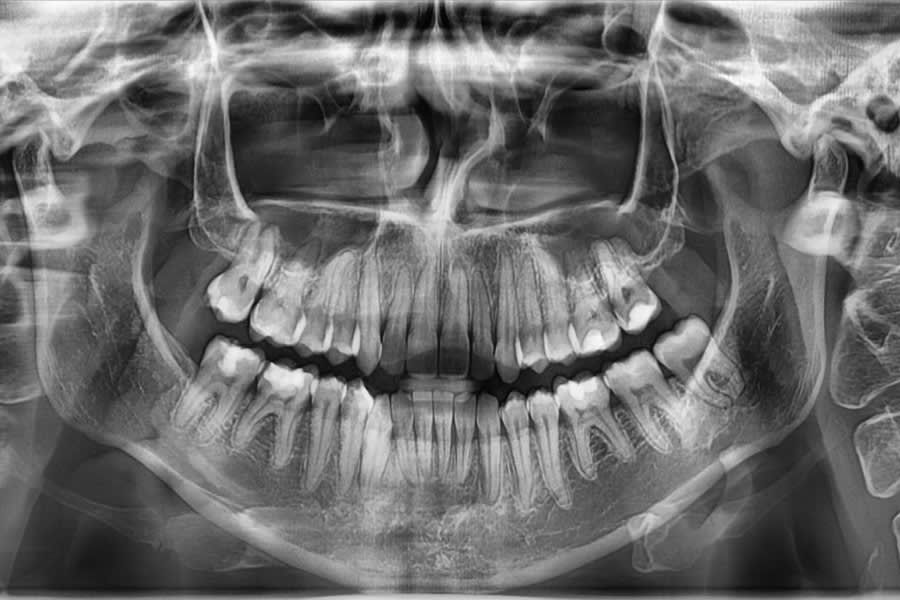

Radiographic Follow-up

Panoramic/cephalometric re-evaluation is used to document posterior intrusion without root resorption or sinus compromise, improved upper incisor angulation in bone, lip profile changes consistent with CCW autorotation, and favorable skeletal parameters.7,17-21 (Figure 18 through Figure 21)